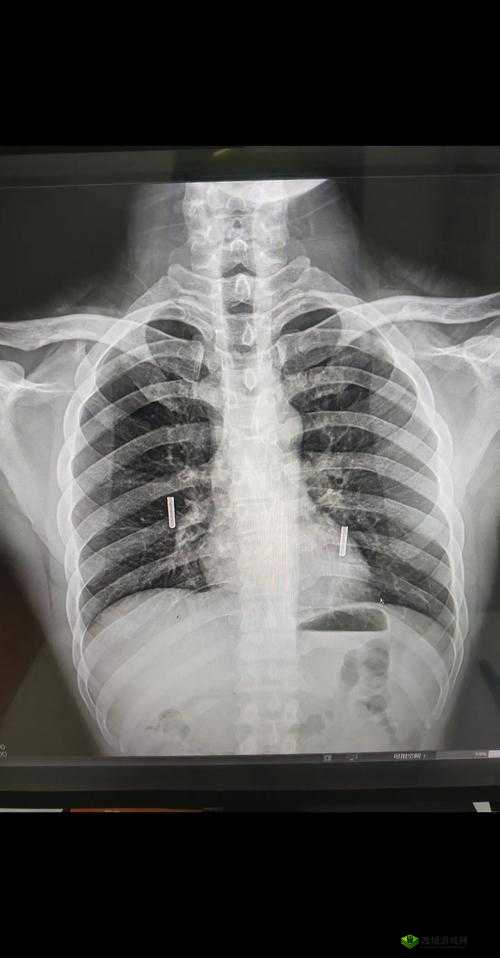

这些胸片,每一张都像是一扇通往未知世界的窗户。它们不仅仅是简单的医学影像,更是一个个扣人心弦的故事载体。或许其中一张胸片,背后隐藏着一段令人痛心的疾病抗争史。那斑驳的影像中,记录着患者与病魔不屈不挠的战斗,每一处阴影都诉说着身体所承受的痛苦与折磨。

又或许有一张胸片,它牵扯出的是一个被忽视的环境问题。也许是长期生活在污染严重的地区,导致肺部出现了难以逆转的损伤,而这张胸片就成为了无声的控诉。它提醒着我们,环境对我们的健康有着多么深远的影响,我们必须要对自己生存的环境负责。

还有的胸片可能与职业相关。那些长期从事高风险工作的人们,他们的肺部在不知不觉中受到了伤害。这张胸片就像是一个警钟,敲响在我们耳边,让我们意识到每一个职业背后都可能隐藏着不为人知的健康隐患。